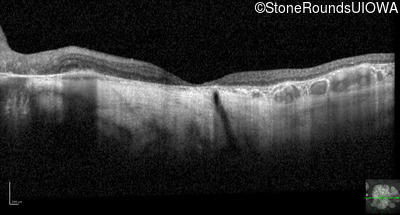

Optical Coherence Tomography - Right - 20/300

Exemplar / OCT Stack